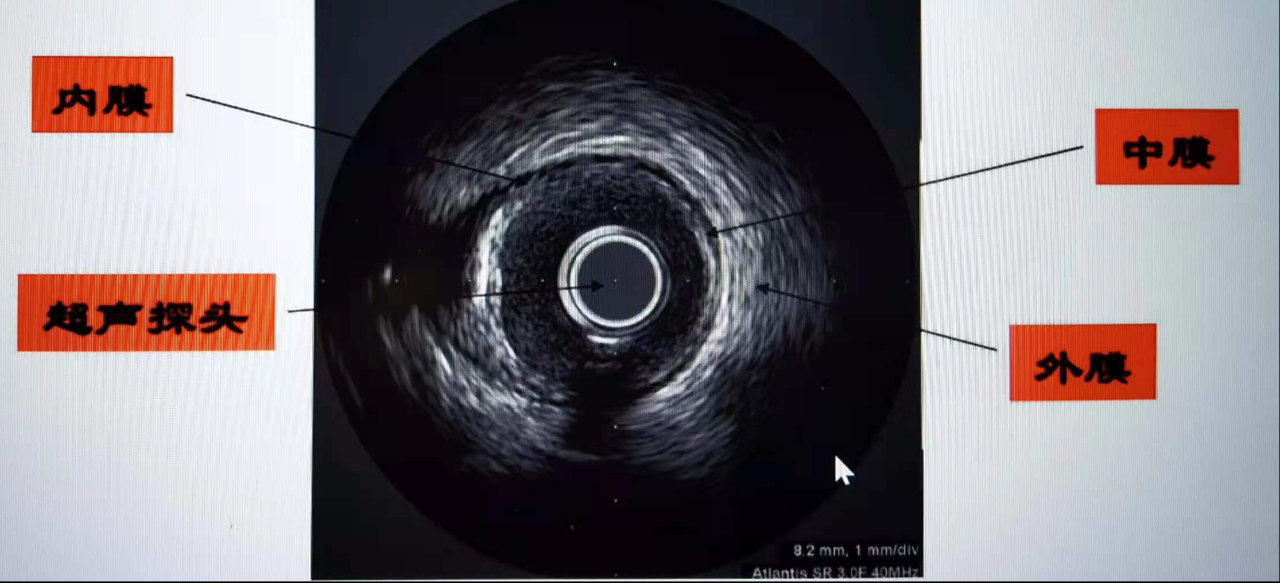

众所周知,心脏、腹部可以做超声检查,血管内超声(Intra Vascular UltraSound,IVUS)技术。简单通俗地说,就是在心脏血管内做超声检查,将微型化的超声探头通过导管的技术送入血管腔内,从而提供管壁在内的横截面图像。精细程度堪称心血管介入术中医生的“火眼金睛”。

目前确诊冠心病的主要手段是冠脉造影,但该技术只能对血管内血流情况进行成像,且容易受造影角度的影响,不能显示病变所在的管壁和粥样斑块,不能提供粥样斑块的形态和性质。IVUS利用安装在心导管顶端的微型超声探头,实时显示血管的截面图像,能清晰显示管壁结构的厚度、管腔大小和形状等,精确地测量血管腔径及截面积,甚至可以辨认钙化、纤维化和脂质池等病变,发现冠脉造影不能显示的血管早期病变,在支架植入前为选择合适的支架提供准确的参考依据,使术者能够更好地选择支架的直径和长度,使支架和血管更好地匹配。在支架植入后,可对支架的大小、位置、形状、贴壁程度、对称性和展开满意度进行系统的评价,保证支架充分而不过度扩张。